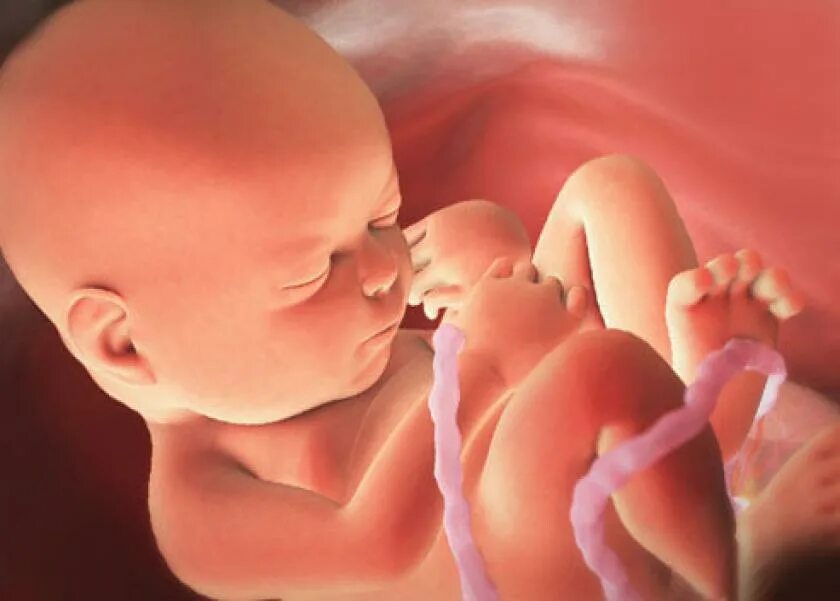

Ребенок 36 недель беременности в животе